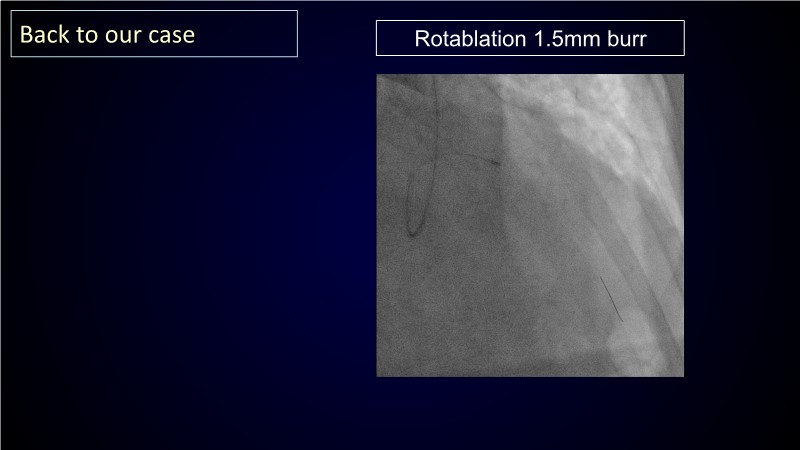

Calcified coronary lesions are a major challenge in PCI. This PCRGulf-GIM 2025 session showcases a complex case with intravascular imaging, highlighting how IVUS 123 guides each step.

From planning the procedure and understanding calcium distribution, to lesion preparation with modern modification tools, and post-PCI assessment to confirm stent expansion and detect complications, this session demonstrates practical, imaging-driven strategies.